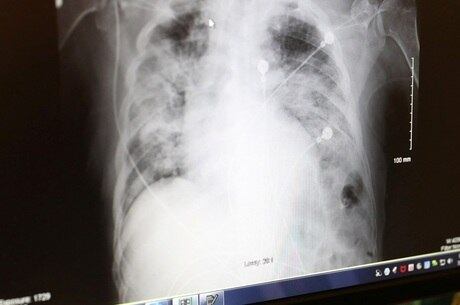

Casos graves de covid-19 podem piorar com pneumonia bacteriana

Pessoas com quadro grave de covid-19 podem vir a desenvolver um quadro chamado de superinfecção. “É quando você desenvolve uma pneumonia bacteriana em cima da pneumonia causada pelo coronavírus”, afirma o infectologista Luís Fernando Waib, da SBI (Sociedade Brasileira de Infectologia).

O quadro é relativamente comum em pacientes graves e piora a situação clínica do infectado. Waib explica que são inúmeras as bactérias que podem causar essa pneumonia e que normalmente elas já estão no corpo do paciente.